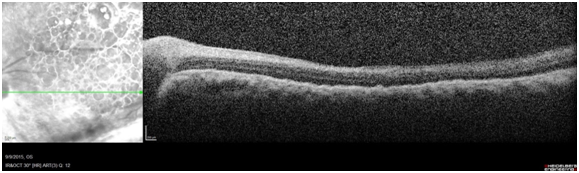

A 35 year-old male with history of open-globe repair from BB gun injury 3 weeks prior presented with light perception vision, vitreous hemorrhage and suspected retinal detachment. He underwent 23-gauge pars plana lensectomy, vitrectomy, membrane peeling, retinectomy, subretinal clots removal, endolaser and silicone oil tamponade (Video). Intraoperatively, a full thickness macular hole (MH), posterior strike site in temporal macula with overlying scar and hemorrhaghic retinal detachment was seen. A pigmented preretinal membrane was covering the posterior pole and peripheral retina. The membrane was very friable and was successfully peeled with flexible loop membrane scraper from the macula and peripheral retina. Macula OCT 2  months later confirmed MH closure (Figure1). At 6 months, visual acuity was counting fingers, the retina was attached and the MH remained closed. Macular holes are found in just 0.15% of eyes with open-globe injury with reported a closure rate of 40%.1,2

Figure 1 Macular spectral domain OCT taken 3 months postoperatively demonstrates completes closure of macular hole.

Figure Title: Post-operative macular OCT.